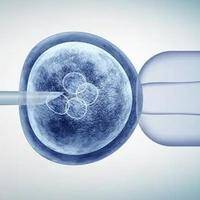

试管移植的优质胚胎怀孕后胎儿会有畸形概率吗?

问题描述:我今年30岁,备孕一年也没有成功怀孕,尝试过几次排卵期同房还是没有成功。就在朋友的建议下去了解了试管婴儿,现在已经试管移植完了,我移植的一枚优质胚胎,我想问问我这怀孕后胎儿会有畸形概率吗?最佳回答:概率很小,在试管婴儿的过程中,医生会对胚胎进行严格的筛选,以选出形态学评分较好的胚胎进行移植。这一筛选过程有助于降低胚胎异常和畸形的风险。因此,从胚胎筛选的角度来看,试管移植的优质胚胎具有较高...